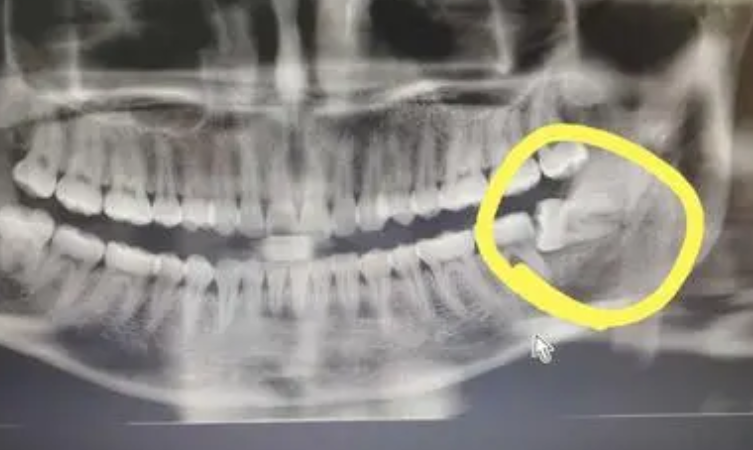

1、拔阻生智齒:拔智齒是這家醫(yī)院很不錯(cuò)的項(xiàng)目之一,醫(yī)生在做阻生和埋伏智齒拔除的時(shí)候,手法都比較細(xì)膩,形成的創(chuàng)口比較小,術(shù)后恢復(fù)的會(huì)比較快。

我的口腔當(dāng)中左側(cè)下面的智齒經(jīng)常會(huì)導(dǎo)致我牙齦疼痛,后來(lái)我才知道,這是因?yàn)檫@個(gè)牙齒有埋伏現(xiàn)象,為了能夠使這顆牙齒帶來(lái)的疼痛快點(diǎn)得到消除,我在南方醫(yī)科大學(xué)珠江醫(yī)院的牙科做了拔智齒的手術(shù)。

拔智齒過(guò)程中